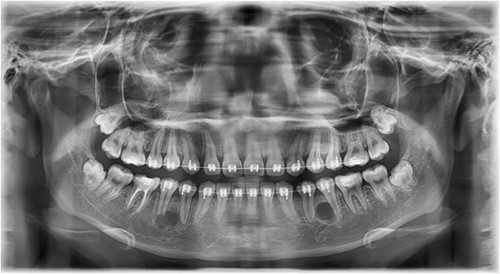

A Neumann full-thickness buccal flap was utilized to remove these during the course of orthodontic treatment. The shortcoming of the buccal surgical removal approach is that although it is better for visualization, it poses a high risk of trauma to the adjacent teeth or nerves [4, 5]. As the premolar was being removed on the right side, there was a fracture of the root apex (Fig. 2). On the left side, the premolar bud could be removed without any trauma to the adjacent tooth roots. After months of follow-up, there was normal bone formation, and no other symptoms were identified (Fig. 3).

Follow-up panoramic 1 week after removal of the supernumerary premolars.